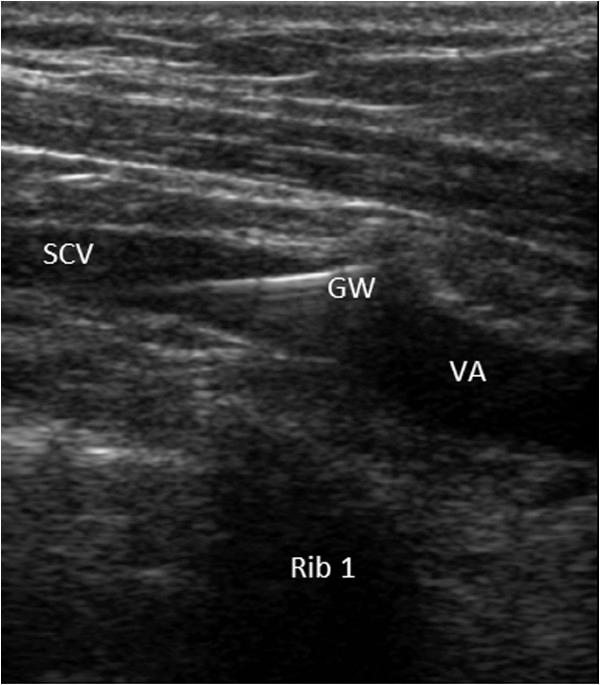

Central venous catheters play an important role in patient care. Real-time ultrasound-guided subclavian central venous (SCV) cannulation may reduce the incidence of complications and the time between skin penetration and the aspiration of venous blood into the syringe. Ultrasonic diagnosis of catheter misplacement and pneumothorax related to central venous catheterization is rapid and accurate. It is unclear, however, whether ultrasound real-time guidance and examination can reduce procedure times and complication rates when compared with landmark guidance and radiographic examination for SCV catheterization.

中心静脉导管在患者护理中发挥着重要作用。实时超声引导下的锁骨下中心静脉(SCV)置管术可能会降低并发症的发生率以及皮肤穿刺至注射器抽吸出静脉血之间的时间。超声对与中心静脉置管相关的导管误置和气胸的诊断快速且准确。然而,与基于体表标志引导和X线检查的SCV置管术相比,超声实时引导和检查是否能减少操作时间和并发症发生率尚不清楚。